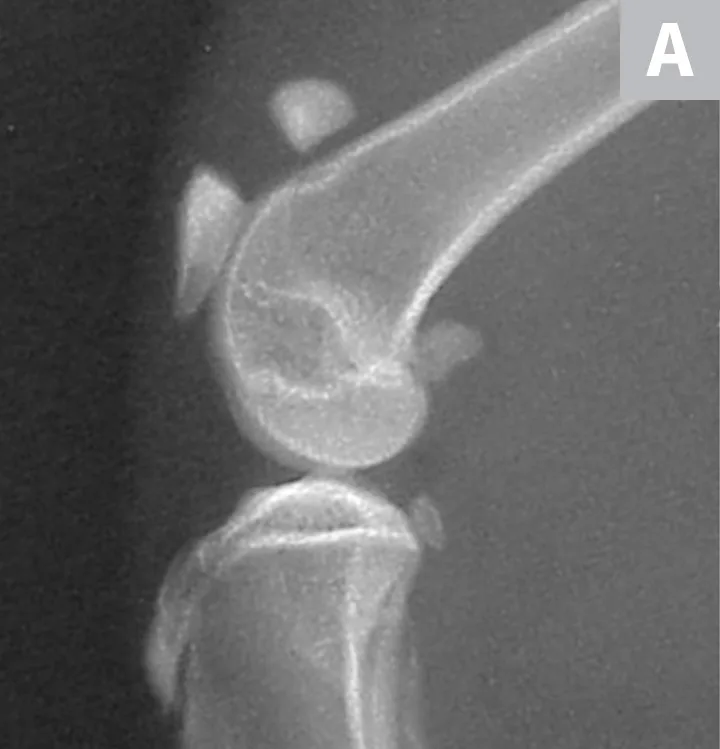

Serial radiographs of the pelvic limbs were taken periodically to monitor progression of the patellar fractures. Comparative orthopedic radiographs (Figure 3) 2 and 8 years after initial presentation revealed persistence of patellar fractures, with fragmentation, progressive sclerosis, and osteophytosis of the left patella.

Radiographs of the patellar fractures taken 2 years (A, left stifle; B, right stifle) and 8 years (C, left stifle; D, right stifle) after initial presentation. Progressive fragmentation and osteophytosis of the left patella and displacement of the right patellar fragments can be seen.